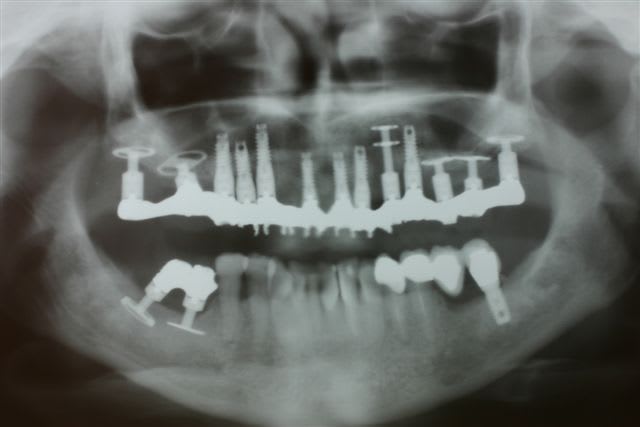

Le cas 2 c est pour plus tard car un peu plus long à expliquer mais là ça commençait par un échec de greffe avec de l iliaque pour remplacer 47 46...

La praticien de la patiente pose ds une greffe molle 3 cylindres et en garde un seul , le mésial et comme par hasard celui qui ds son os natif et pas ds le greffon

Je lui ai posé une première fois une plaque sans ostéotension car cela n existait pas à l époque... Mierda la plaque s expose en lingual et je dois me résoudre à la dépose :-(

Je laisse le site au repos et je viens qques moins plus y reposer un monodisk 8G2DM7 avec apport de nanobone et prfs... Encore mierda il se mobilise et se fibrose

Entre temps je lui fais 3 séances d ostéotension manuelle qui rend le site un plus vascularisé et donc pus exploitable... Je me décide à déposer ce disk en vue simplement de refermer le site sur un nouvel apport de nanobone et là lors de la dépose le site m inspire : bien sanglant et très belle os corticalisé sous le disk : je me jette ds la bagarre et je repose de suite un 9G2DM que je peux bien bolquer avec une vis d ostéosynthèse en vestibulaire ds cette belle corticale sous le disk. Nanobone + PRF + Membrane de Jason...et laissé en enfoui qques mois

Au bout de ces qques mois prise d empreinte sur un disk sonore comme un cylindre et totalement fixe sans l ombre d une sensibilité

Evidemment cette patiente m a tjs posé bcp de question mais je lui avais posé au maxillaire une plaque et un disk qui s étaient intégrés sans aucun ennui donc elle savait que seule de mauvaises circonstances nous avaient empêché de réussir ds le secteur 40

Entre la greffe et mon dernier disk 7 ans sont passés mais je pense que c est effectivement le fait d intervenir plusieurs fois en dépériostant et donc en dévascularisant le site qui nous fait aller ds le mur... En fait j ai laissé de long tps morts pour que l os récupère et j ai choisi de réimplanter de suite lors de la dernière dépose pour éviter encore une meurtrissure supplémentaire pour ce site par un n-ième passage chirurgical à cet endroit

C est pas tellement praticien dépendant mais ça nécesite de raisonner plus que pour la pose de simpe cylindres ds des kms d os alvéolaire

J'ai attentivement regardé ton cas , notamment au max... je trouve impressionnant le nombre d'implant que tu mets...

pour une arcade complète... 13 pour le haut... je penses que 10 suffisent largement... peux tu expliquer ce choix? et deuxième point comment explique tu le problème gingival entre 12 et 11?

C'est vraiment pour le débat, parce que autrement ta gestion de l’Échec mand est vraiment top et comme tu as une philosophie de traitement différente de la mienne, j'aime bien comprendre les raisonnements des autres...ça aide a avancer...

Premier précepte de l implanto basale : tjs duu fixe

Deuxième précepte de l implanto basqle : tjs des ancrages postérieurs donc on va loin au bout des max et mand même si tu peux trouver ça inutile ds un premier tps

Troisième précepte de l implanto basale : qd les volumes sont réduits comme ici où tout le secteur distal est en mono disk ou pire même en plaque, on augmente le nombre d implants au max pour répartir les forces... Il ne faut jamais perdre de vue que même si c est très solide une fois intégré, on passe par la MCI où la solidité est précaire au début...